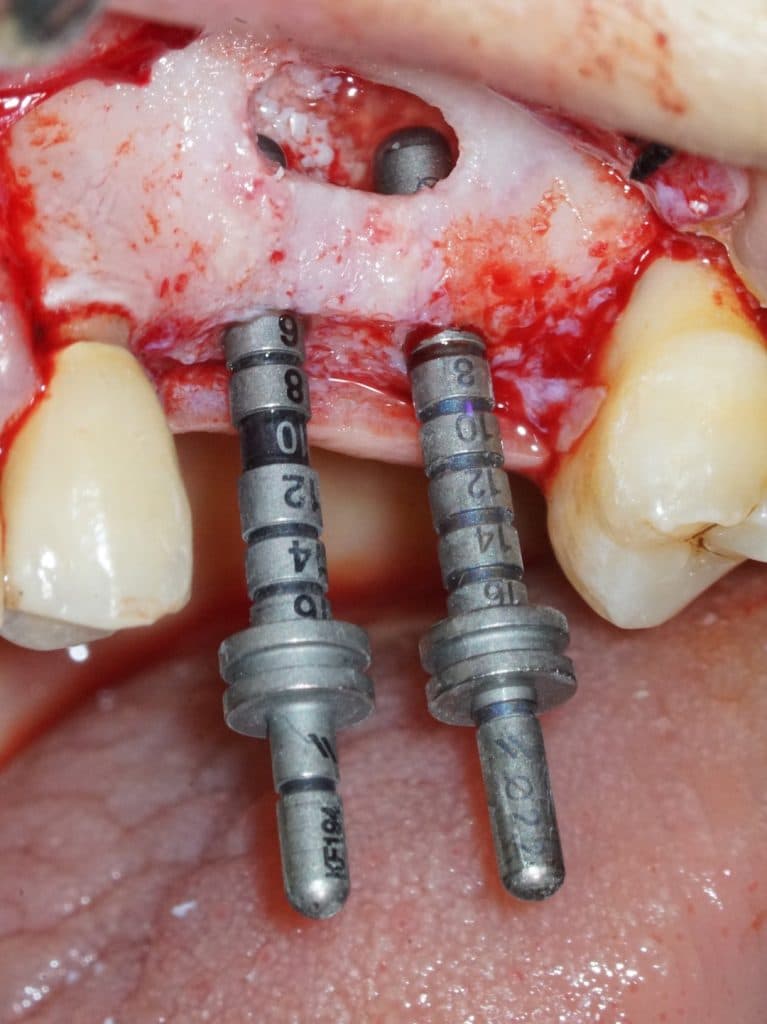

- Two implants are placed drilling the 3 mm of residual crestal bone

- To drill the holes it is recommended to use vibrating burs mounted on a sonic handpiece

- You can see the apexes of the depth indicators inside the maxillary sinus